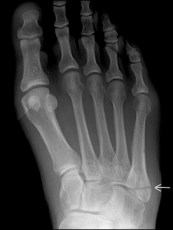

HAIRLINE fractureIn college, I turned my ankle playing basketball.  It became swollen, rather painful, but with Time, the ankle seem to return to good health.  But as the years went by, I would have recurring problems with that ankle.  Then finally I had that foot and ankle x-rayed.  And lo and behold … they found a hairline, stress fracture in my ankle.  And because of that hidden fracture, my ankle had lost it integrity.  So often, this is the case … the fractures within, the hidden fractures, result in an ongoing lack of integrity.